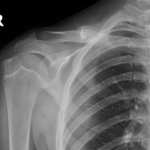

The initial assessment involves detailed history examination and review of previous x-rays. Specialized x-rays are usually required to complete the assessment. The initial assessment and discussion often takes an hour.

During the adjustment phase the patient is followed up in the rooms every two weeks with clinical examination and x-rays. A close scrutiny is maintained to identify any complications early.

During the adjustment phase, the patient is followed up in the rooms every two weeks with clinical examination and x-rays. Close scrutiny is maintained to identify any complications early.